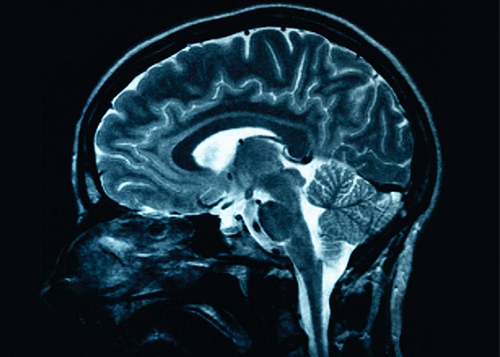

Medical Express рассказывает об уникальной системе - портативном сканере головного мозга. Известно, что стандартные МРТ-сканеры дороги, требуют специальной инфраструктуры и немобильны.

Группа исследователей из Массачусетской больницы общего профиля разработала недорогой, компактный, портативный и маломощный магнитно-резонансный томограф, который может быть установлен в машине скорой помощи, доставлен прямо в палату пациента или установлен в небольших клиниках и кабинетах врачей по всему миру.

Уже создан портативный прототип сканера для МРТ головного мозга, который можно подключить к стандартной розетке и который гораздо меньше производит шума, чем традиционные сканеры МРТ. Сам магнит в сканере размером с корзину для белья, а общий вес всей системы, включая магнит, катушки, усилители, консоль и тележку, составляет 230 килограммов.

Сканер легко перевозит на тележке один человек. При желании вес возможно уменьшить до 160 килограммов. В ходе тестирования на трех здоровых взрослых добровольцах сканер смог успешно сгенерировать трехмерные изображения мозга. В среднем на это уходило 10 минут.